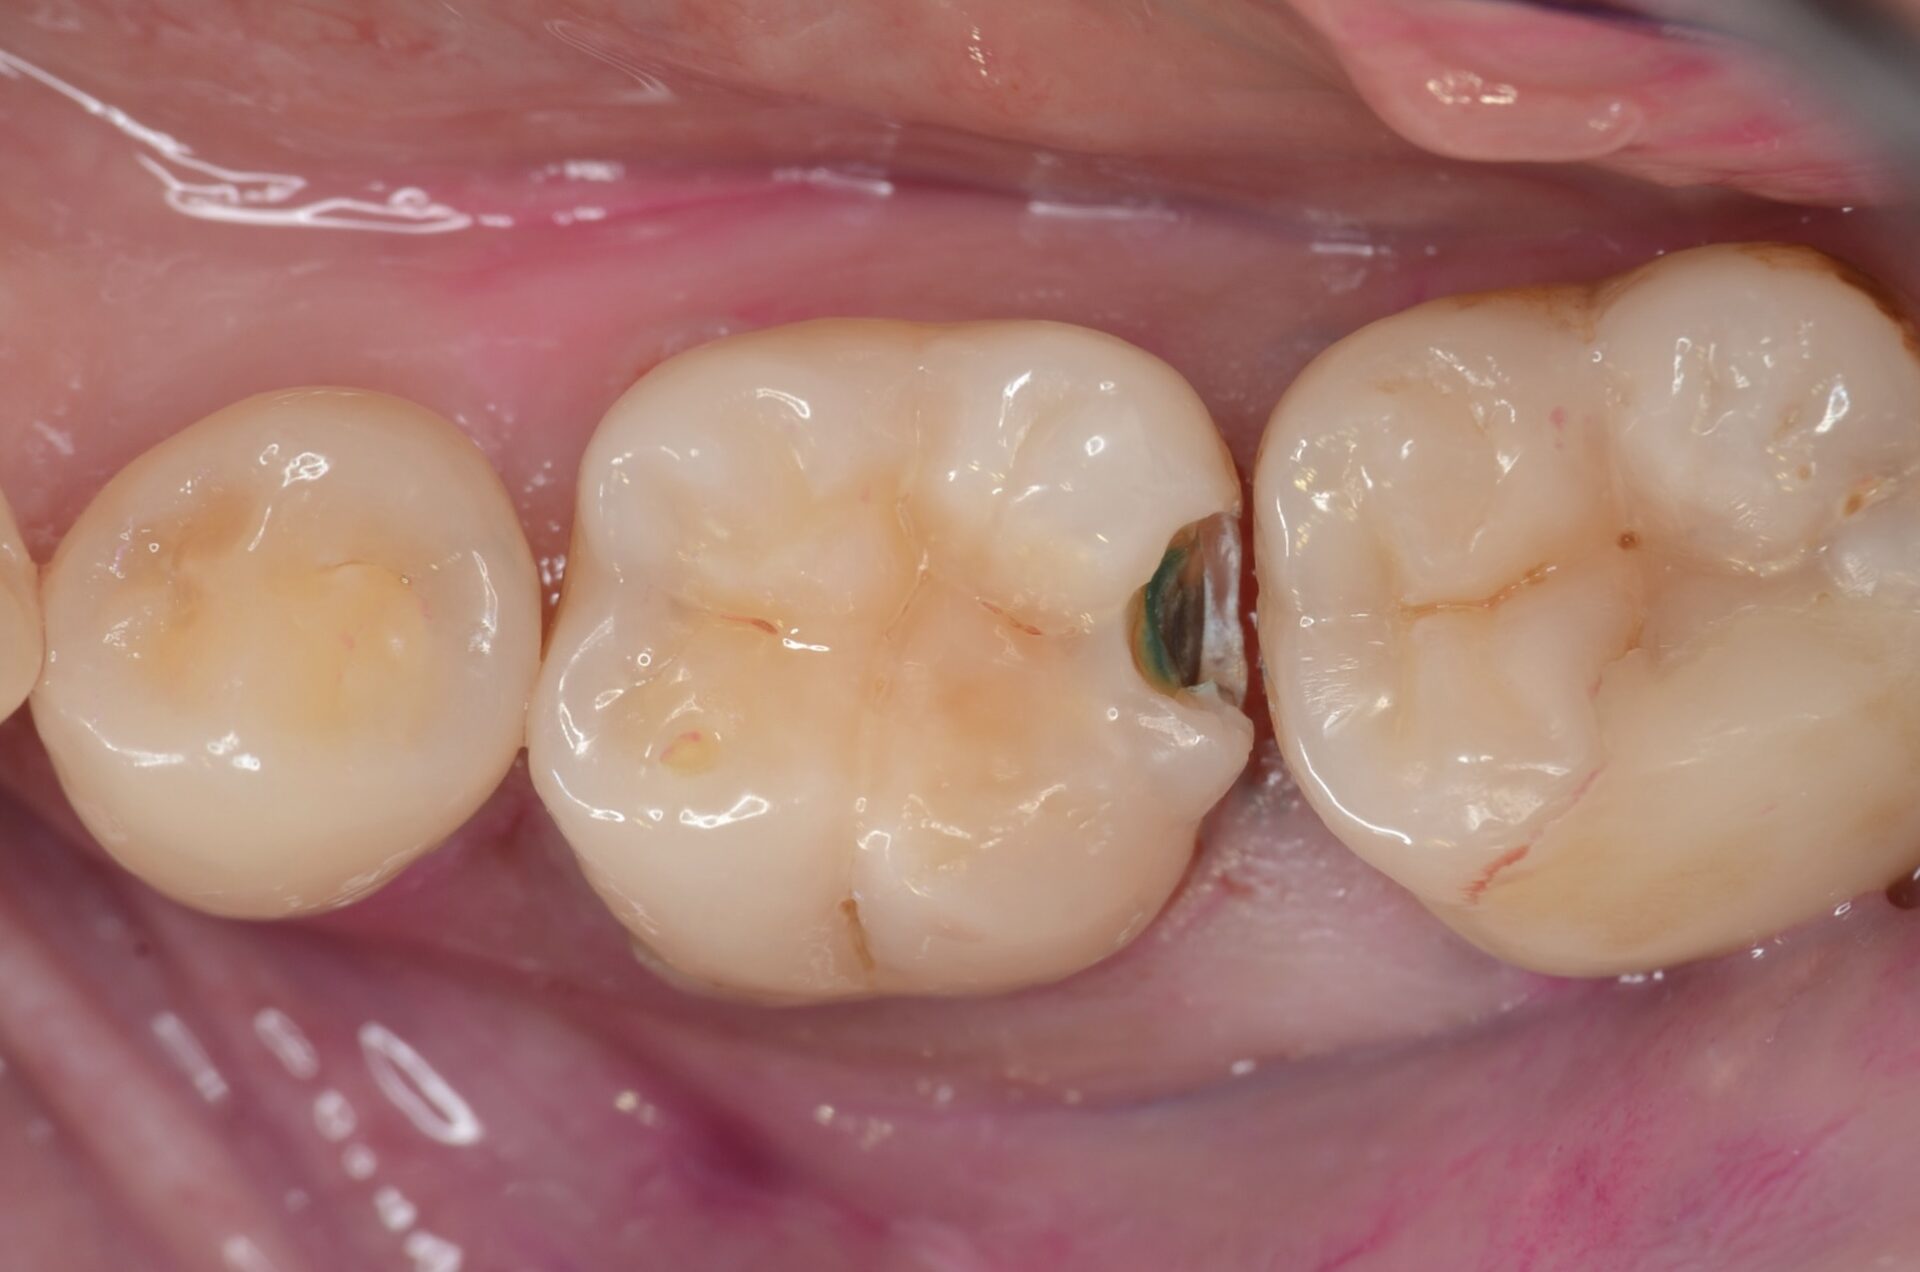

試し削り

X線写真では虫歯が大きい事を確認しています。少し削って中の虫歯を確認しました。やはり虫歯は大きいようです。ラバーダムが装着時に破れないように、先に隣接面の虫歯をとり歯質を整える場合もあります。 -

ラバーダム装着後、虫歯完全除去

虫歯治療においてもラバーダム装着は必須です。 唾液や血液から歯面が汚染されるのを防ぎ、乾燥状態を保つラバーダムは、接着力を向上させるためにも大切なアイテムです。 虫歯を完全に削りました。 -